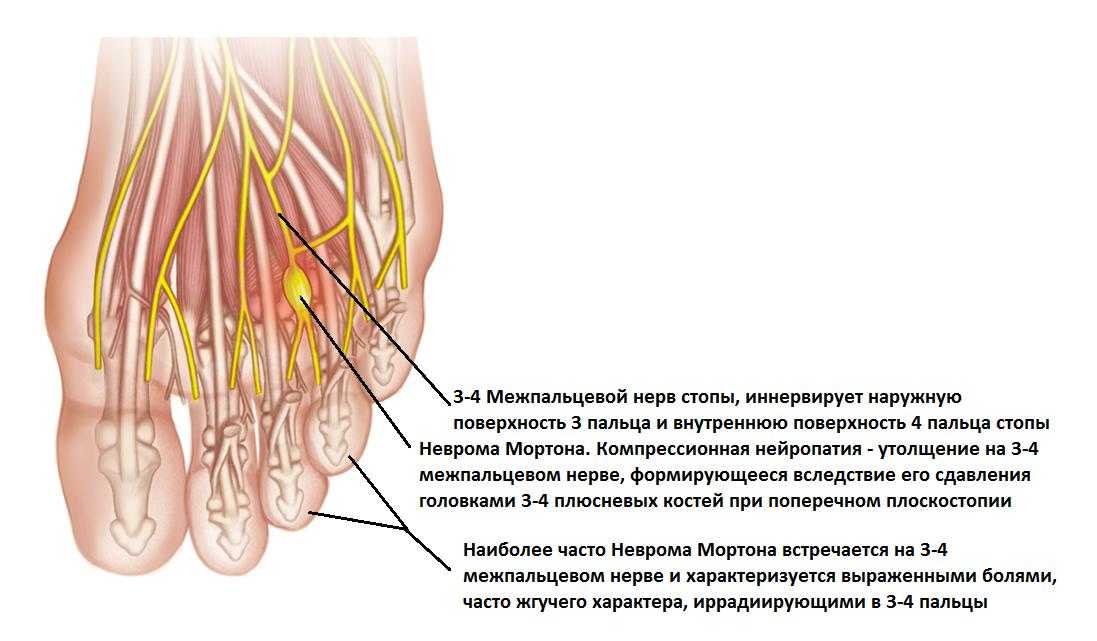

Разрастание нервной ткани, расположенной на подошве ноги, между 3-и и 4-м пальцами, называется невромой Мортона. Что это такое? Это фиброзное доброкачественное новообразование обычно поражает одну ногу, редко – обе сразу.

Заболевание проявляется в виде утолщения нерва на подошве, это сопровождается сильными болями, резко ограничивает человека в передвижениях. Когда у врачей появляется подозрение на развитие метатарзалгии Мортона, это говорит об опухолевом новообразовании нервной ткани, вызывающем сильные боли в плюсневых сочленениях.

По анатомии на этом участке стопы нерв делится на ветви, направляющиеся к боковым поверхностям пальцев, боль расходится именно в этих направлениях. По отзывам пациентов, столкнувшихся с невромой Мортона, они уже знают, что это такое и как лечить патологию, чтобы не довести болезнь до операции.

Начало заболевания проявляется слабым ощущением сдавливания в зоне 3-го и 4-го пальцев. Уже такой симптом должен насторожить человека, показать ему, что в работе ноги произошел сбой. При дальнейшем развитии болезни симптомы постепенно нарастают.

- боли, жжение, потеря чувствительности в области 3-го и 4-го пальцев;